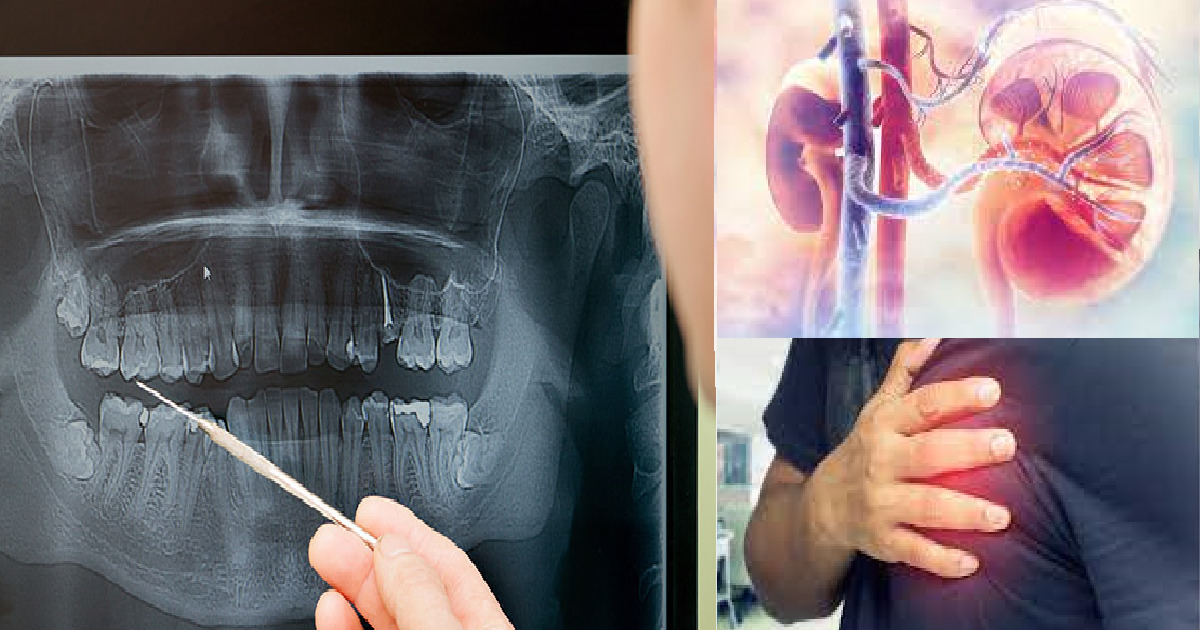

Unbehandelte Zahnprobleme können weitreichende Auswirkungen auf Ihre Gesundheit haben. Viele Menschen glauben, dass Probleme in der Mundhöhle nur die Zähne betreffen, aber das Gegenteil ist der Fall. Hier ist eine Liste von Gesundheitsproblemen, die entstehen können:

- Entzündete Arterien

- Geschwollene Beine

- Erkrankungen des Herzens, der Nieren, der Augen oder der Gelenke